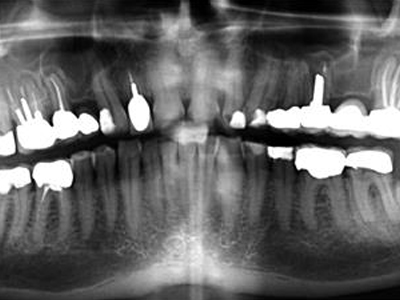

Clinical & Radiographic Monitoring :

Healing is assessed by clinical signs and radiographic changes in the periapical tissue over time, with complete healing sometimes taking several years